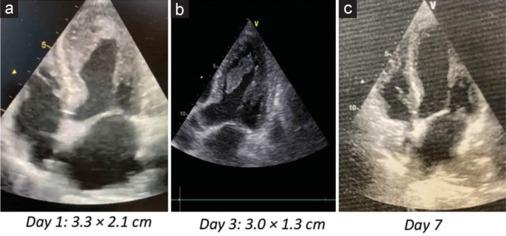

Left ventricular thrombosis (LVT) in stress cardiomyopathy or Takotsubo syndrome (TTS) is a moderately frequent complication. However, cardioembolic events are not frequently reported. Herein, we present a case report of 80-year-old patient admitted for chest pain at rest, started few days earlier following a violent argument. Her medical history included arterial hypertension and recent surgery of descending colon adenocarcinoma. Electrocardiogram showed sinus rhythm, negative T waves from V1 to V6, in D2, D3, AVF, and long QTc. Laboratory examinations documented an increased high sensitivity Troponin I, myoglobin, creatine kinase-MB, and B-type natriuretic peptide. Transthoracic echocardiography (TTE) showed a reduced left ventricular (LV) ejection fraction, "apical ballooning" with hyperkinesis of the basal segments of LV, suggestive for stress cardiomyopathy. A large thrombus in LV apex (3.3 cm × 2.1 cm) was found. Coronary angiogram showed normal coronary arteries. Anticoagulant therapy with Warfarin was quickly started, bridging with unfractionated heparin. Cardiac surgery was excluded for high-risk surgical patient. Daily TTE monitoring was done with evidence of slight reduction of the LVT. After 7 day from admission, the patient complained an intense and sudden pain in lower extremities bilaterally. An acute occlusion of the descending aorta just above the bifurcation in the common iliac arteries was found. Interventional radiology procedure of recanalization of the bis-iliac carrefour was successfully performed. However, few hours after the procedure, the patient's hemodynamic conditions worsened until the exitus.

应激性心肌病或Takotsubo综合征(TTS)中的左心室血栓形成(LVT)是一种较为常见的并发症。然而,心脏栓塞事件的报道并不常见。在此,我们报告一例80岁患者,因静息时胸痛入院,胸痛始于几天前的一次激烈争吵之后。她的病史包括动脉高血压和近期降结肠癌手术。心电图显示窦性心律,V1至V6、D2、D3、AVF导联T波倒置,QTc间期延长。实验室检查显示高敏肌钙蛋白I、肌红蛋白、肌酸激酶-MB和B型利钠肽升高。经胸超声心动图(TTE)显示左心室(LV)射血分数降低,LV基底部节段运动亢进伴“心尖部气球样变”,提示应激性心肌病。在LV心尖部发现一个大血栓(3.3 cm×2.1 cm)。冠状动脉造影显示冠状动脉正常。迅速开始使用华法林进行抗凝治疗,并使用普通肝素进行桥接。因患者手术风险高,排除心脏手术。每天进行TTE监测,结果显示LVT略有缩小。入院7天后,患者双侧下肢突然剧烈疼痛。发现腹主动脉在双侧髂总动脉分叉上方急性闭塞。成功进行了双侧髂动脉分叉处再通的介入放射学手术。然而,手术后数小时,患者的血流动力学状况恶化直至死亡。